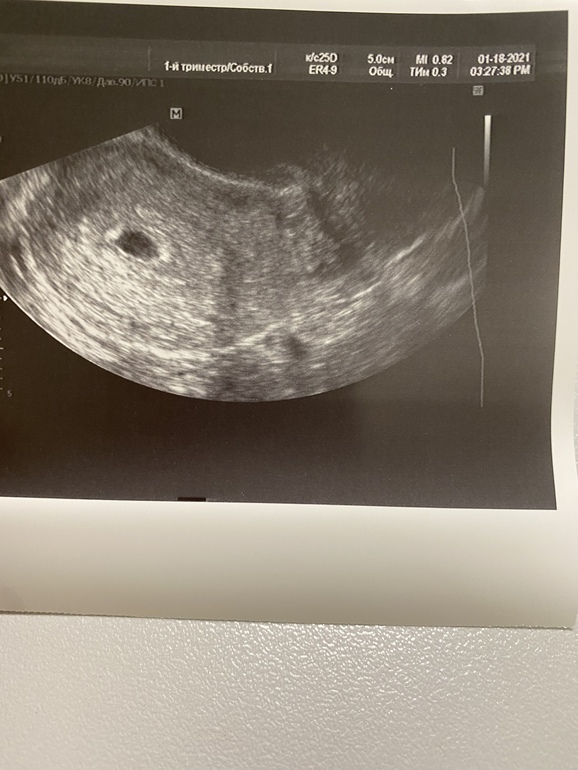

Первое УЗИ 🥰 меняю значок

По узи все хорошо, плодное яйцо в матке 6.1мм, желточный мешок 1,5мм все соответствует сроку ❤️ (Сегодня 21 ДПО примерно)